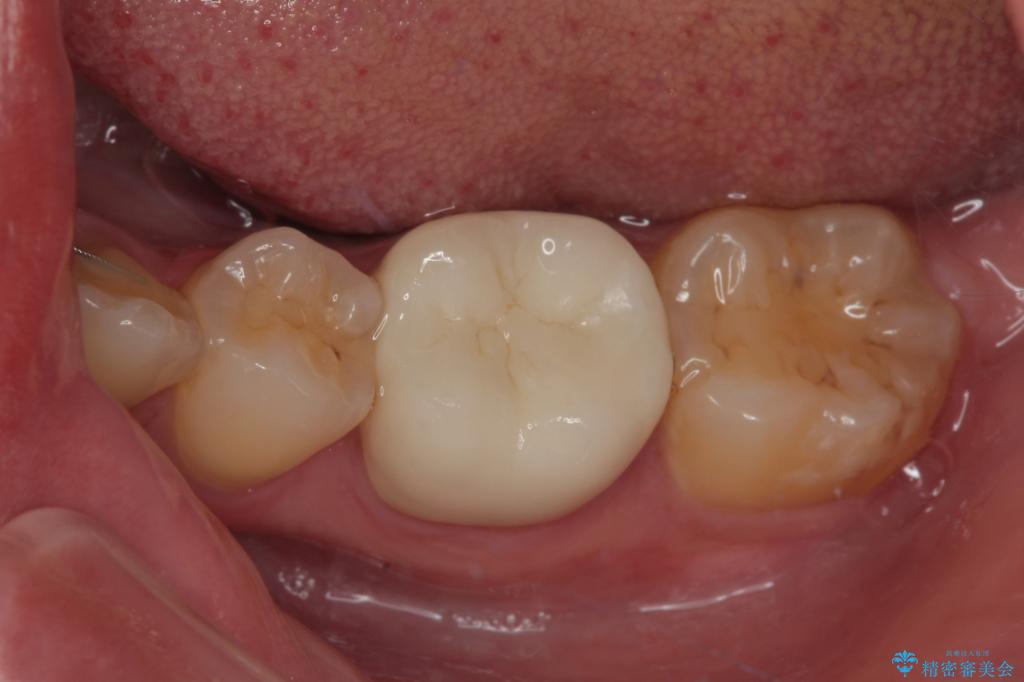

虫歯による不快な症状がなくなり喜んでいただきました。セラミックの被せものが入った後の違和感なく過ごせているそうです。矯正治療終了直後の被せもの治療なのでリテーナーの作成回数をできるだけ少なく迅速に行うことを考慮して治療を行いました。

今後、ホワイトニングを行う予定なので、患者様のご希望により、周りの歯に比べてあえて白い被せものを作成しました。